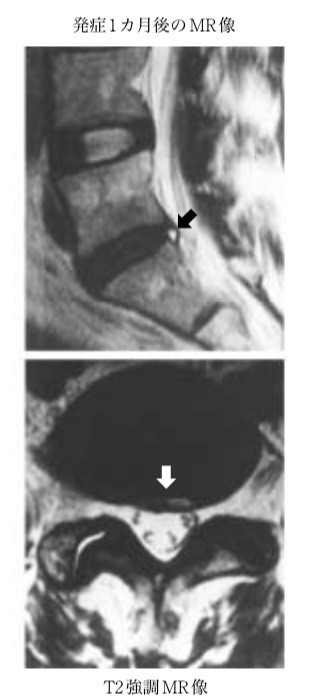

矢印のところが椎間板が痛んで炎症し痛みを引き起こしている場所です。

以前は両側性の痛みが多いと言われていましたが、この論文からだと片側も50%は認められたということです。 痛みは動けなくなるくらい痛みや 前かがみをすることで痛いことが多いです。

炎症期はそらしても痛いです。 発生するきっかけは ・何気ない動作 ・ものを取るときに前かがみになった ・中腰での動作 ・重いものを持ち上げる 特に何気ない動作が一番多いです。 治療は炎症由来なのでロキソニン内服とコルセットをして安静にすればすぐに痛みが落ち着きます。

椎間板の痛みなので腰の筋肉をマッサージしても改善はしません。 炎症が落ち着けば痛みはほぼ落ち着き時間と共に改善します。